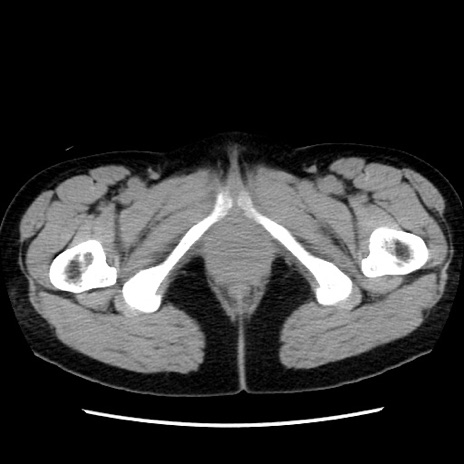

症例10(横断像)

【症例】 50歳代女性

【主訴】 腹痛

【現病歴】前日生レバーを食べた。今朝に排便あり。 昼前に突然発症の腹痛を生じ、当院救急外来を受診した。

【既往歴】 子宮筋腫にてで子宮全摘後

【身体所見】 意識清明、腹部:平坦、軟、下腹部やや左を中心に圧痛・反跳痛あり、筋性防御あり

【データ】WBC 7800、CRP 0.07